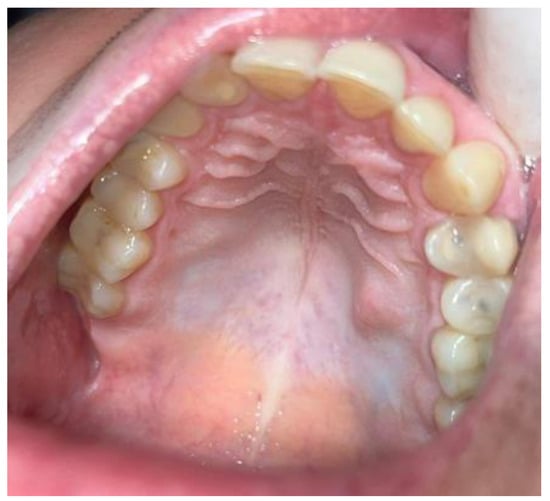

2. Case Description